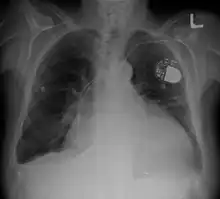

La cardiomégalie est une augmentation anormale de la taille du cœur[1]. Elle peut être dépistée par une radiographie thoracique de face, en position debout, montrant un index cardiothoracique supérieur à 0,5 ou 0,55. Cet index est égal au rapport entre le plus grand diamètre horizontal du cœur et le plus grand diamètre horizontal du thorax, mesurés sur une radiographie thoracique conventionnelle.

Un « gros cœur » peut être du, soit à une augmentation d'une ou plusieurs cavités cardiaques, par exemple dans le cadre d'une cardiomyopathie dilatée, soit à un épaississement important des parois des ventricules cardiaques (hypertrophie ventriculaire gauche dans le cadre d'une cardiomyopathie hypertrophique). Il peut également parfois témoigner d'un épanchement péricardique. Ces différents diagnostics sont tranchés par une échocardiographie.